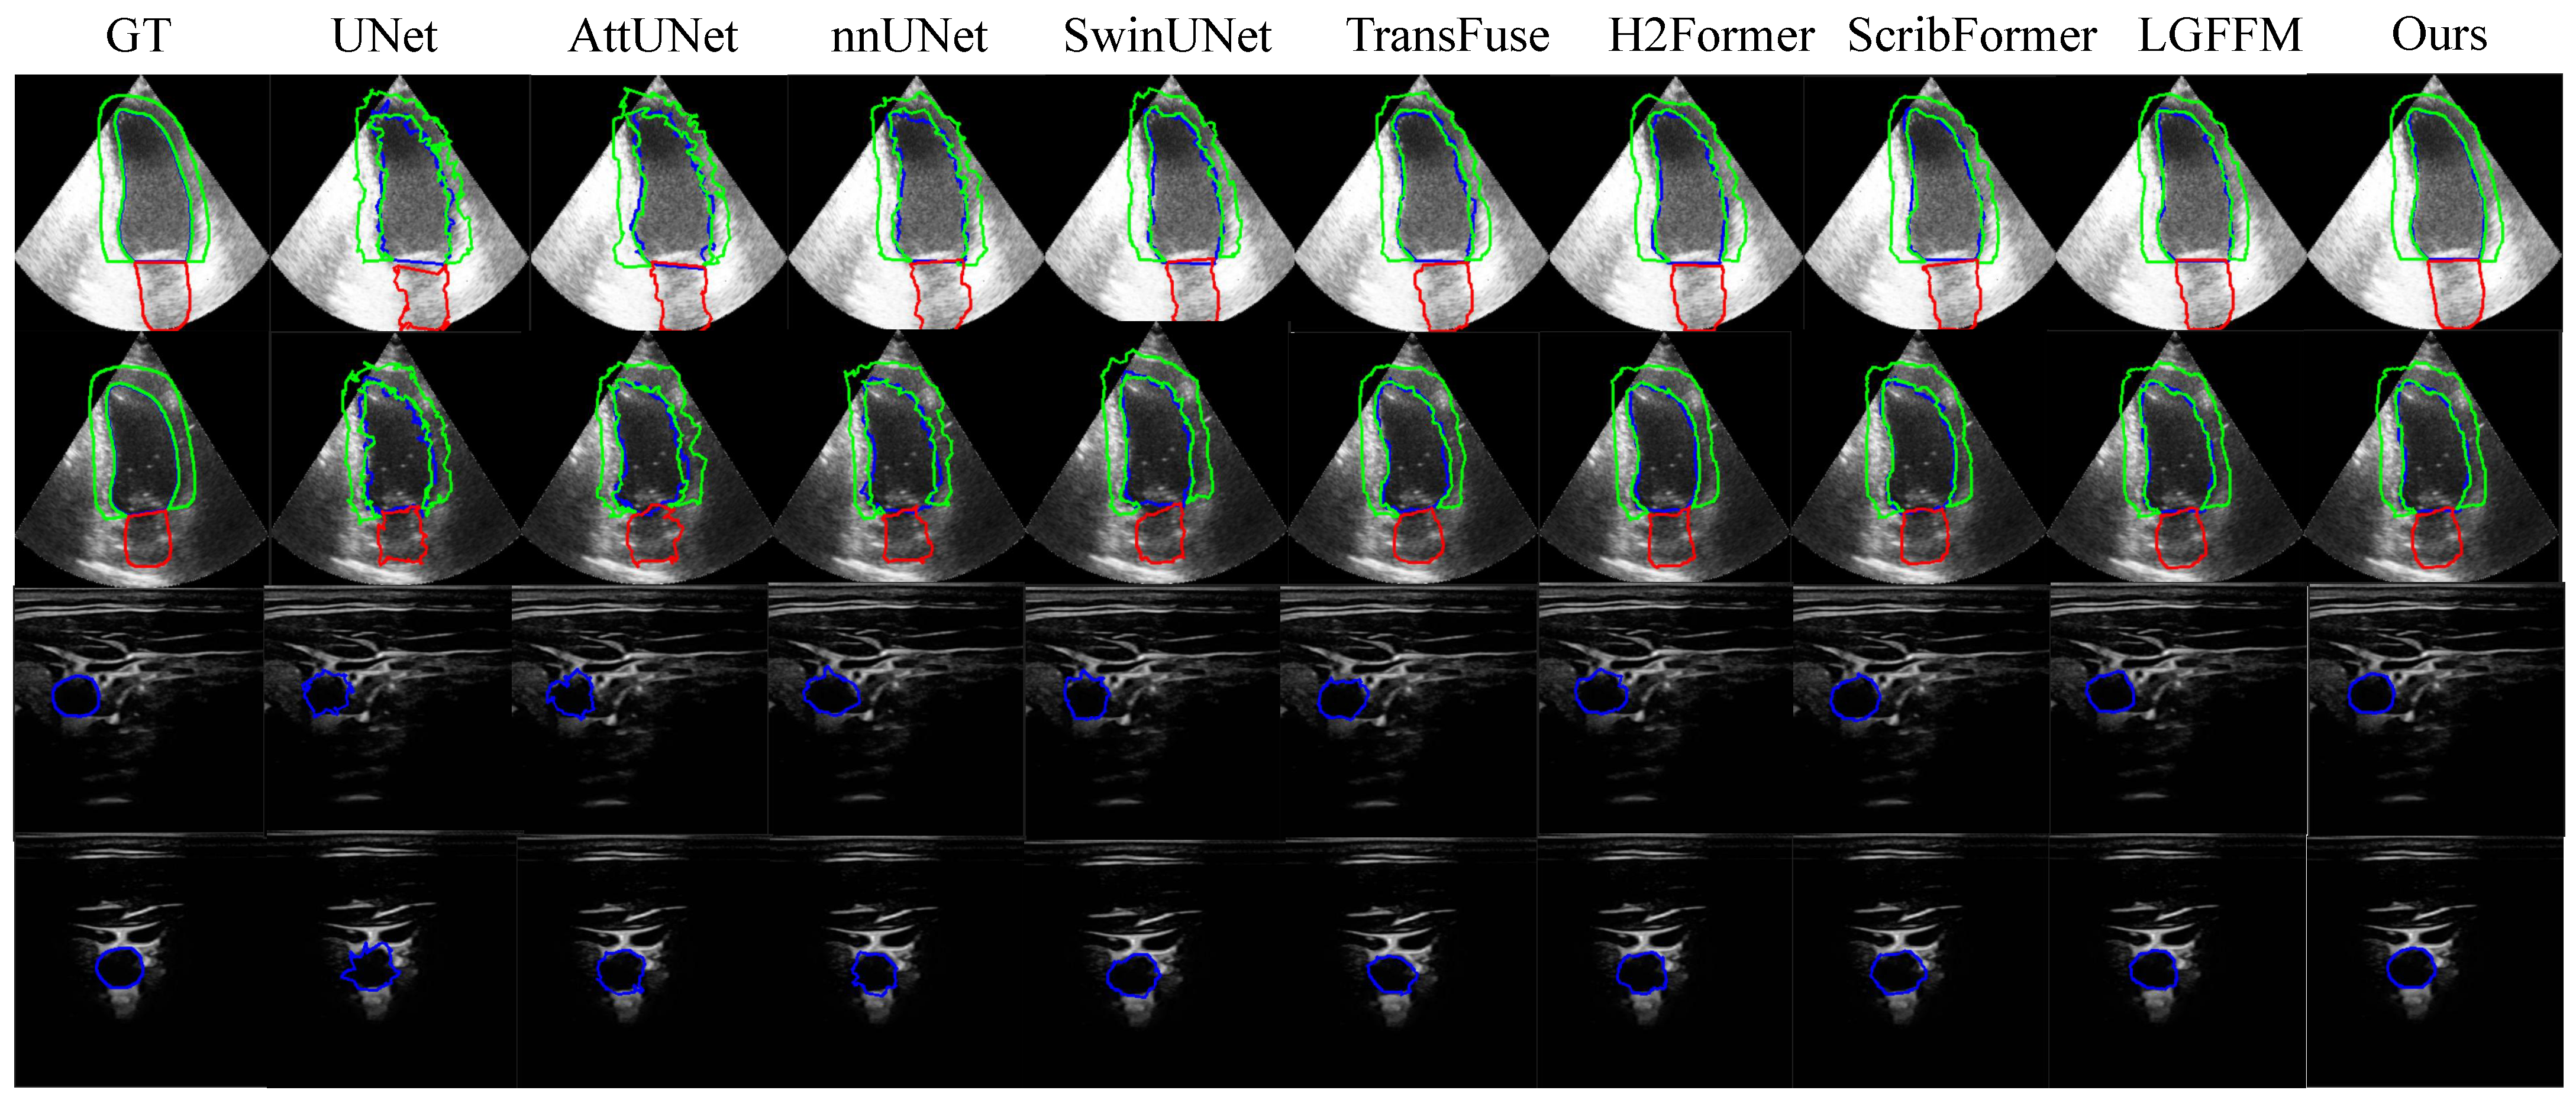

4.3. Result Analysis

4.3.1. The Results of CCAUI and CAMUS

4.3.2. The Results of DDTI and TN3K

4.3.3. The Results of HC-18 and JNU-IFM